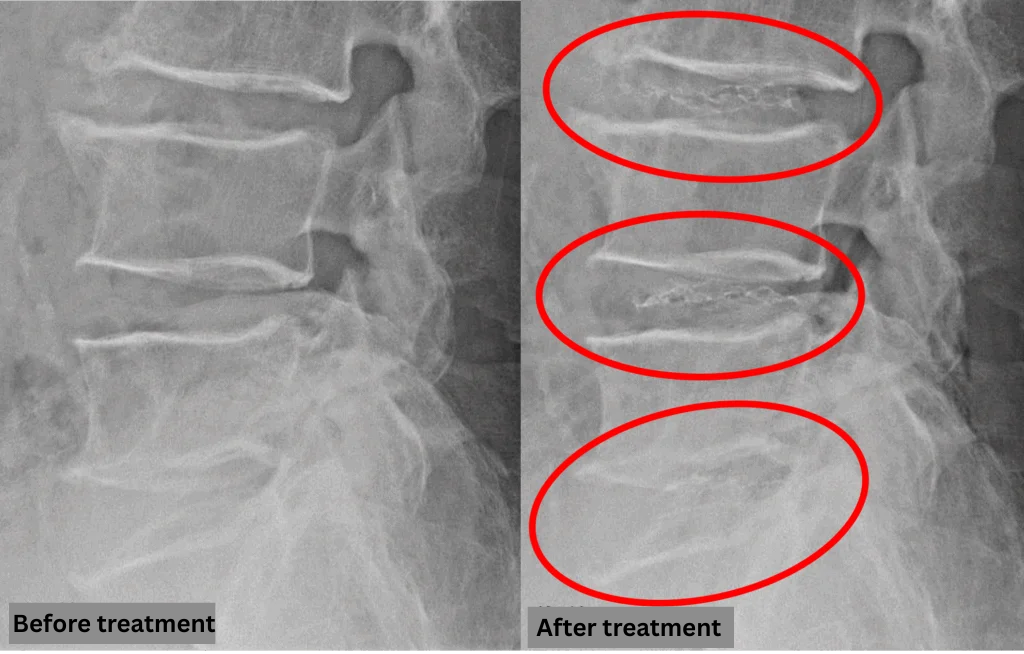

Imaging and findings

- L3/4, L5/S1 – Disc degeneration, protrusion

- L4/5 – Disc degeneration, disc herniation

The above findings were also observed on the imaging.

Findings show that spinal canal compression on discs L3/4, L4/5, and L5/S1 is the most likely cause of symptoms.

After consulting with the patient, the Cellgel Method was performed on L3/4, 4/5 and 5/s.